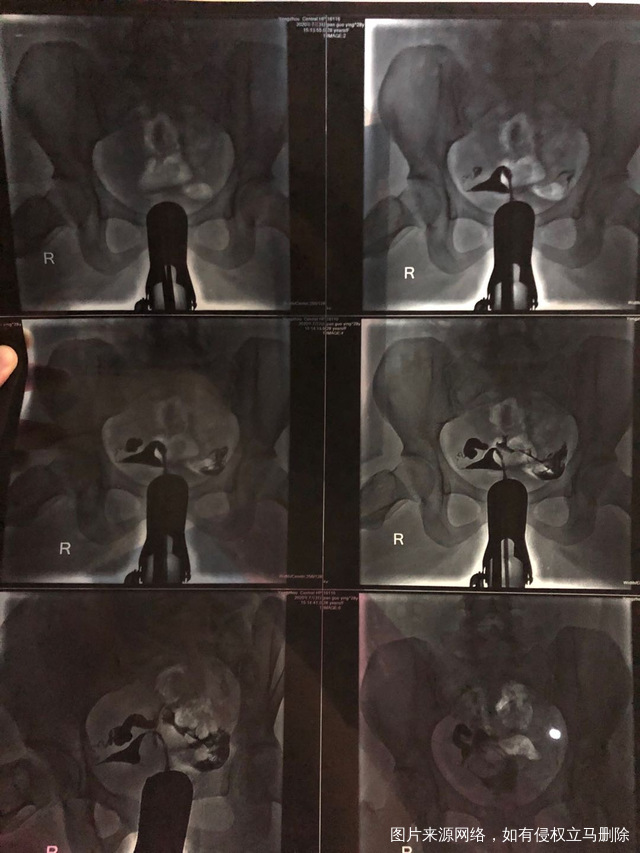

辛苦各位医生帮分析一下这个造影片子怎么备孕好

辛苦各位医生帮分析一下这个造影片子,怎么备孕好,谢谢🙏